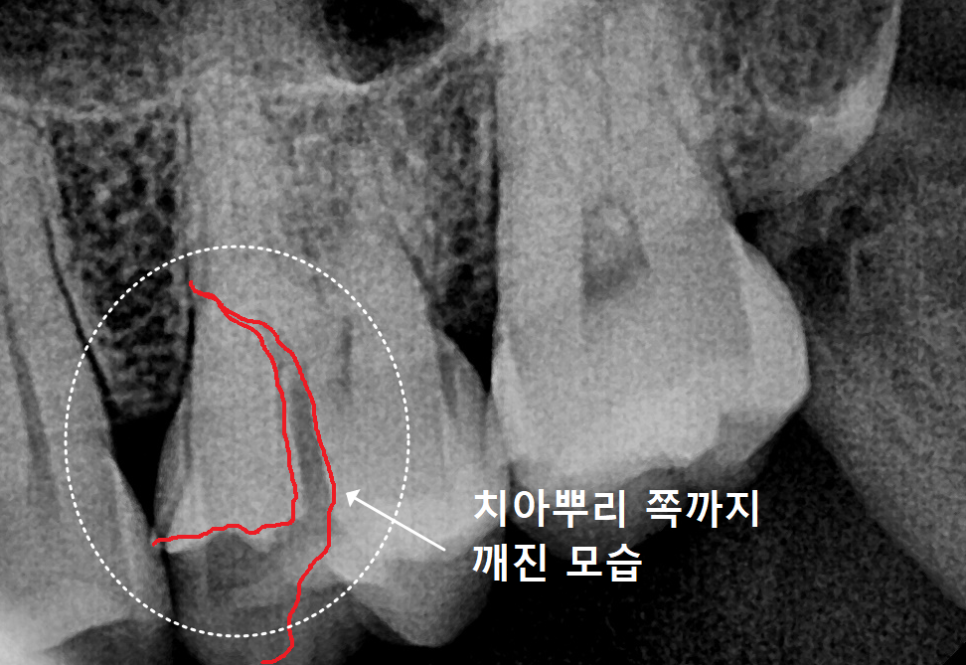

250529 치아파절로 인해 깨진 조각

250529 방사선 사진상 치아 뿌리 쪽까지 금이 가 있는 모습